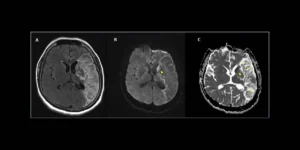

NeuroCovid : les trois stades d’atteinte du système nerveux par le Covid-19

NeuroCovid : les trois stades d'atteinte du système nerveux par le Covid-19 Les orages cytokiniques causés par le Covid-19 sévère pourraient entraîner des dommages cérébraux à long terme, parmi lesquels la maladie d'Alzheimer, alertent des neurologues américains. De la perte d'odorat à la maladie d'Alzheimer, le virus du Covid-19 semble...Cart